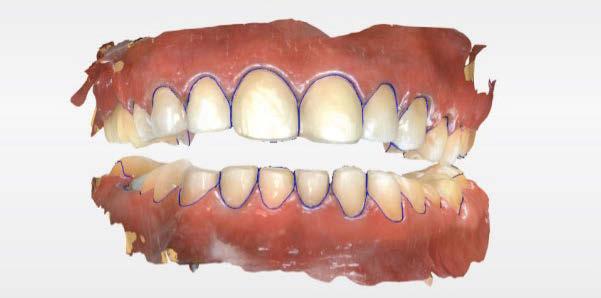

Acude a la consulta un paciente masculino de 35 años exigiendo cambios en la estética de sus dientes. El examen intraoral clínico y fotográfico reveló pérdida de estructura dentaria con facetas de desgaste en dientes anterosuperiores e inferiores, acentuándose hacia zonas oclusales de dientes posteriores.

El diagnóstico evidenció que el paciente presentaba alteración en la dinámica de la guía anterior por el desgaste de los bordes incisales, con pérdida de dimensión vertical oclusal (VDO), alteración del plano de oclusión y relaciones interoclusales inestables (Figuras 1 y 2)

Se obtuvieron modelos de estudio (Figuras 3-6) digitales mediante un escáner confocal de luz azul estructurada (PrimeScan, Dentsply Sirona) y se planificó un protocolo de desgaste mínimamente necesario y conservador de las estructuras

Figura 1. Caso inicial. Figura 2. Vista oclusal superior.

Figura 5. Impresión digital, vista superior derecha. Figura 3. Escaneado maxilar superior zona anterior. Figura 4. Impresión digital, vista superior izquierda.

Figura 6. Impresión digital, vista oclusal, maxilar inferior.